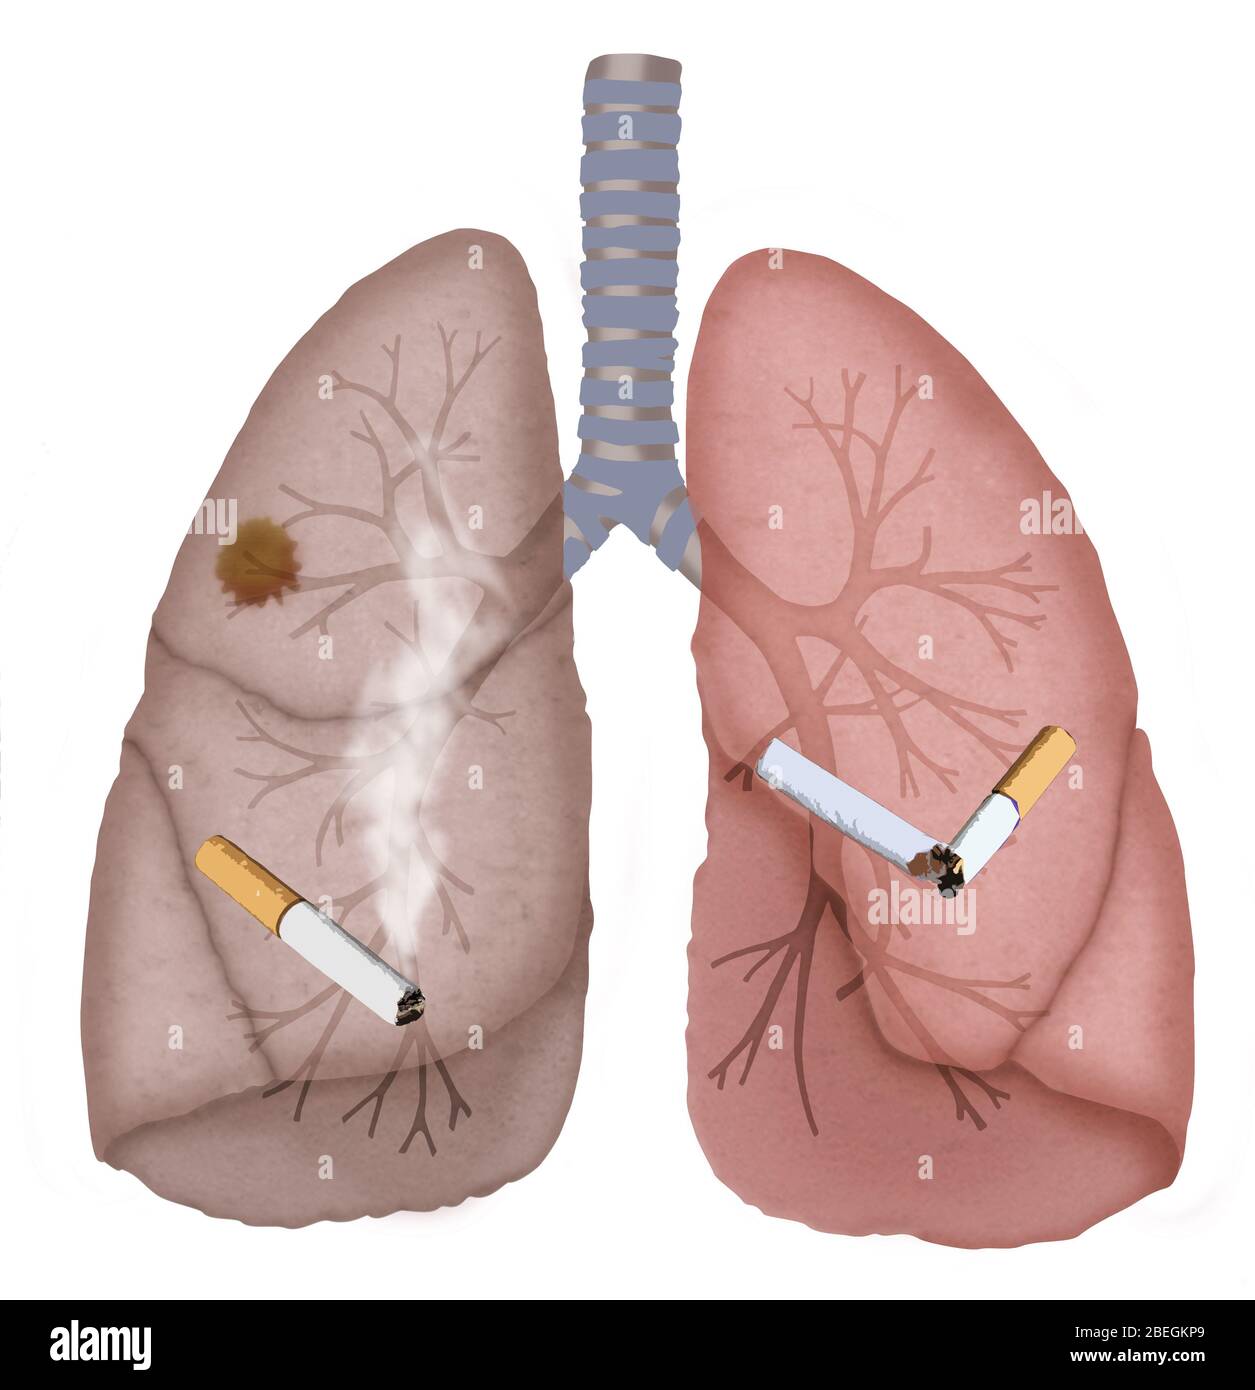

Lista es una colección y muestra de imágenes sobre imagenes de pulmones sanos y enfermos realizada por upup.edu.vn. Además, hay imágenes relacionadas con imagenes de pulmones sanos, imágenes de pulmones sanos, radiografía de pulmones sanos y enfermos, fotos de pulmones sanos, radiografía pulmones sanos y enfermos, rayos x de pulmones sanos y enfermos, pulmon sano y enfermo, pulmón sano y enfermo . Para más información, consulta a continuación.

imagenes de pulmones sanos y enfermos

Posts: imagenes de pulmones sanos y enfermos